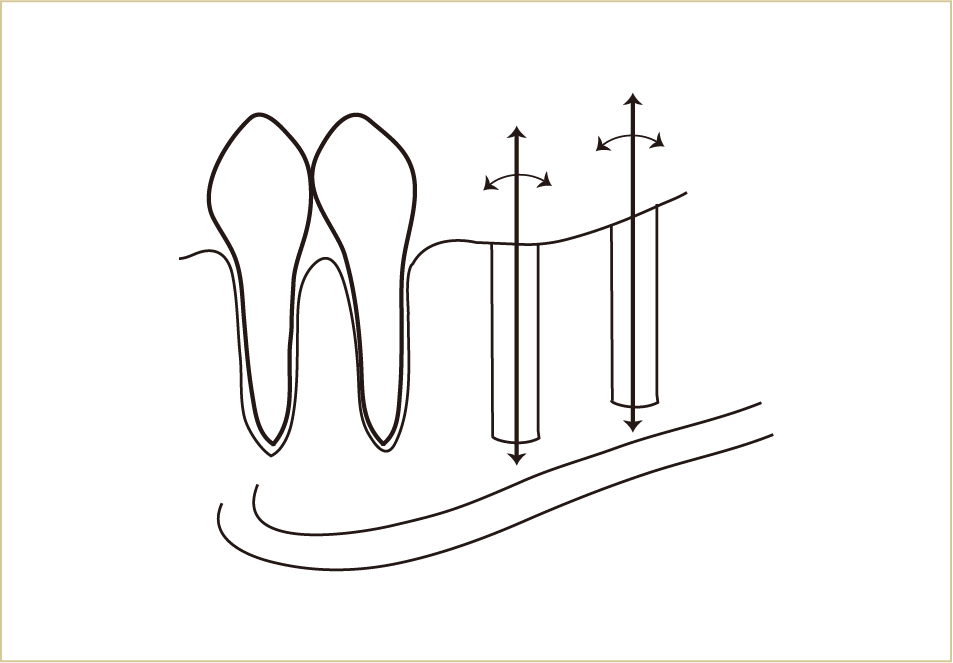

CTで、インプラント自体の方向、傾き、深さを立体的に決めることができるようになった。

3次元的な診断ができるようになったことで、より正確に治療計画を立てて手術することができるようになった。

CTによって、かなり高い精度で骨の構造が立体的に把握できるようになりました。最近では、このCTのデータをパソコン上でコンピューターガイドシステムとして手術のシミュレーション計画を立て、実際の外科手術を行う際に、反映させることもできるようになってきています。

CT上でインプラントを立てる位置、方向、長さ、深さなどを決定して、それを誘導するマウスピースのようなもの(サージカルテンプレートという)をつくり、それをガイドとして実際の手術を行います。